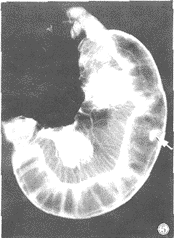

小腸腫瘤1.X線鋇餐檢查,對疑有十二指腸的腫瘤.採用弛張性十二指腸鋇劑造影。

2.纖維十二指腸鏡、纖維小腸鏡檢查及選擇性動脈造影術.可提高小腸腫瘤的診斷率。

小腸腫瘤1.腹痛為常見症狀,可因腫瘤表面潰爛、刺激腸管引起腸痙攣所引起,也可因腸梗阻或腸套疊所致。當腫瘤巨大、突入腸腔,可引起腸堵塞;腫瘤侵犯腸壁可引起腸管狹窄、梗阻。這類梗阻較多見於小腸惡性腫瘤。腸套疊多半是小腸良性腫瘤所致。可急性發作,也可反覆慢性發作。